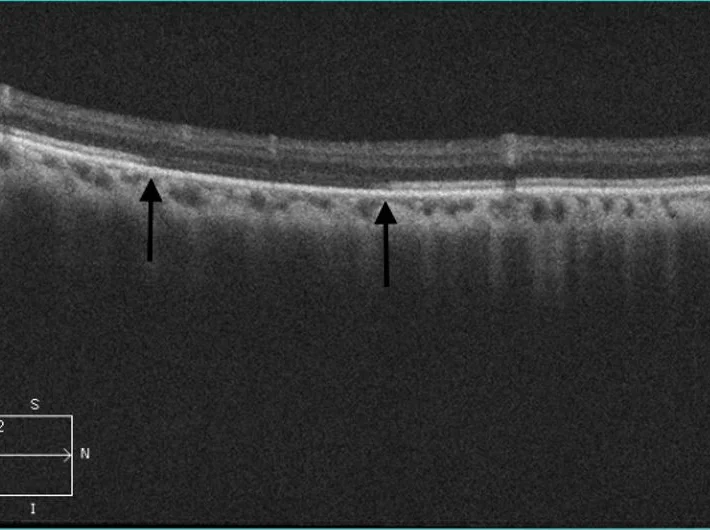

Abstract: Commotio retinae is a common manifestation of blunt trauma to the eye. This case report follows the clinical course of a patient presenting with commotio retinae after being struck with a kicked soccer ball. It highlights the clinical value of ocular coherence tomography in documenting and identifying various morphologic changes from blunt trauma over time.